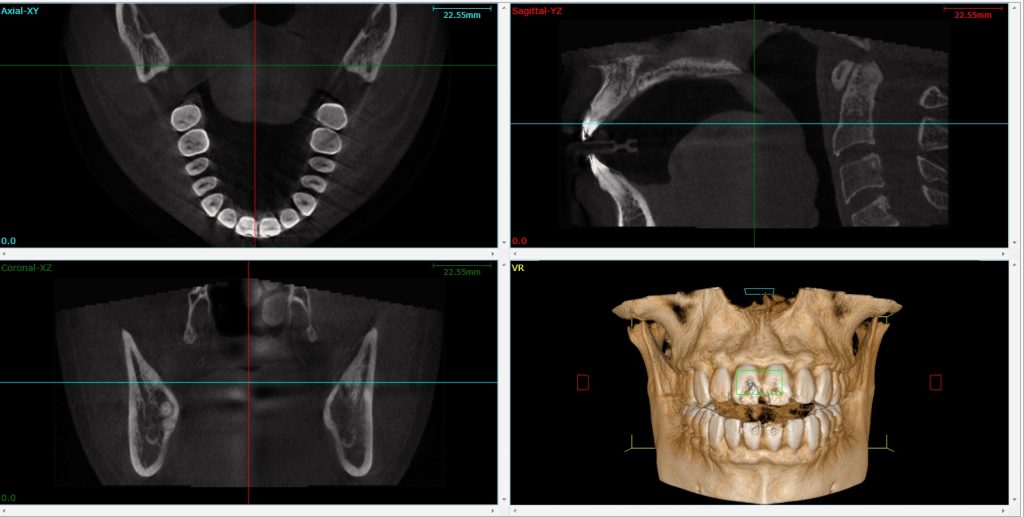

Dental imaging software SmartVPro LargeV Instrument for dental Dental Imagery learn about dental radiography techniques, maxillofacial imaging, and the role of diagnostic radiographers in dentistry. since then, dental imaging has seen tremendous progress and its applications in various fields of dentistry. the use of ai technology in dental imaging marks a revolutionary development that will usher in a time of. Find resources on scope of practice, radiation. Dental Imagery.

CBCT Dental Diagnosis With Deep Learning Syntec Optics Dental Imagery learn about dental radiography techniques, maxillofacial imaging, and the role of diagnostic radiographers in dentistry. since then, dental imaging has seen tremendous progress and its applications in various fields of dentistry. the use of ai technology in dental imaging marks a revolutionary development that will usher in a time of. Find resources on scope of practice, radiation. Dental Imagery.